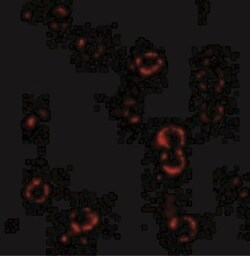

CXCR4 Polyclonal specifically detects CXCR4 in Human, Mouse, Rat samples. It is validated for Western Blot, ELISA, Immunohistochemistry, Immunocytochemistry/Immunofluorescence, Immunohistochemistry-Paraffin, Knockdown Validated.

| Western Blot 1-2 μg/mL, ELISA 1:100-1:2000, Immunohistochemistry 5 μg/mL, Immunocytochemistry/Immunofluorescence 4 μg/mL, Immunohistochemistry-Paraffin 5 μg/mL, Knockdown Validated | |